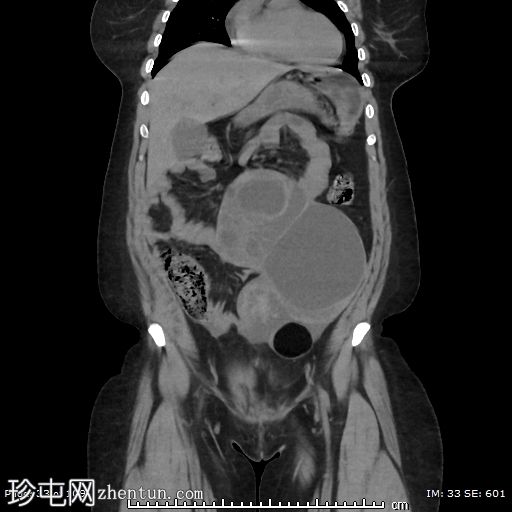

冠状位平扫

左侧附件区可见一巨大囊性病变,大小约9 x 12 cm,主要呈液体密度,囊壁光滑薄。

邻近一复杂囊性成分,向中线延伸,大小约10 x 9 cm,内部可见分隔及不均匀液体密度,提示内容物可能为出血性或部分复杂性。

左侧附件区可见一边界清晰的卵圆形低密度肿块,大小约4 x 4 cm,囊壁厚,内部为软组织、脂肪和液体混合密度,符合成熟囊性畸胎瘤(皮样囊肿)的影像学表现。

左侧附件血管蒂扭转,形成血管和软组织呈漩涡状排列,高度提示卵巢扭转。

可见轻度卵巢周围脂肪条索状改变和少量邻近盆腔积液,可能为继发性充血和水肿。

由于左侧附件增大的组织结构压迫,子宫向右侧移位。